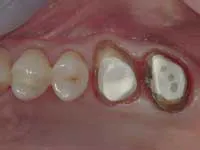

Less than one-half of the coronal tooth structure remaining (Figs. 1-6)

It is my opinion, regardless of the other factors present, that it is still advisable to place a post or posts in such teeth. Endodontically treated teeth with less than one-half of the coronal tooth structure remaining have a reduced chance of long-term service, and patients should be so advised as the treatment plan is developed.